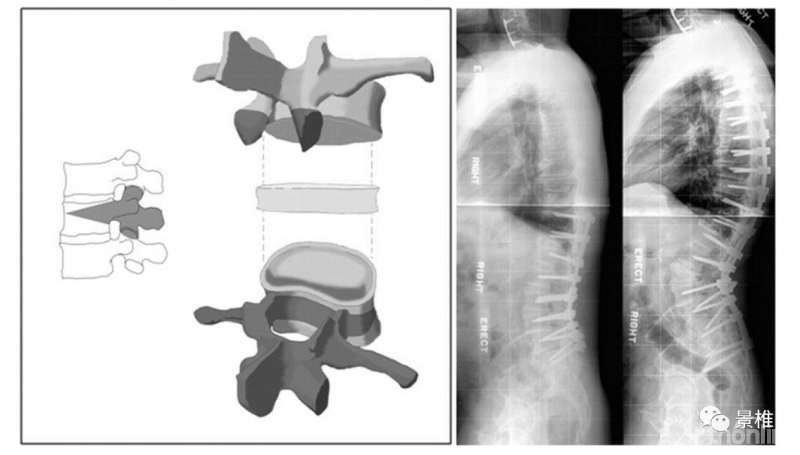

3级 PSO

3级,椎体内截骨,1、2级把关节突、椎板、棘突等后柱结构都切了,3级就再切一部分前中柱吧。

要先切除椎弓根,以免闭合后神经被挤压。再经两侧椎弓根残端楔形切除部分椎体骨质,所以叫PSO(Pedicle Subtraction Osteotomy)。后凸矫形30º。

PSO图解:

单椎体PSO可矫正约20°~30°的后凸。